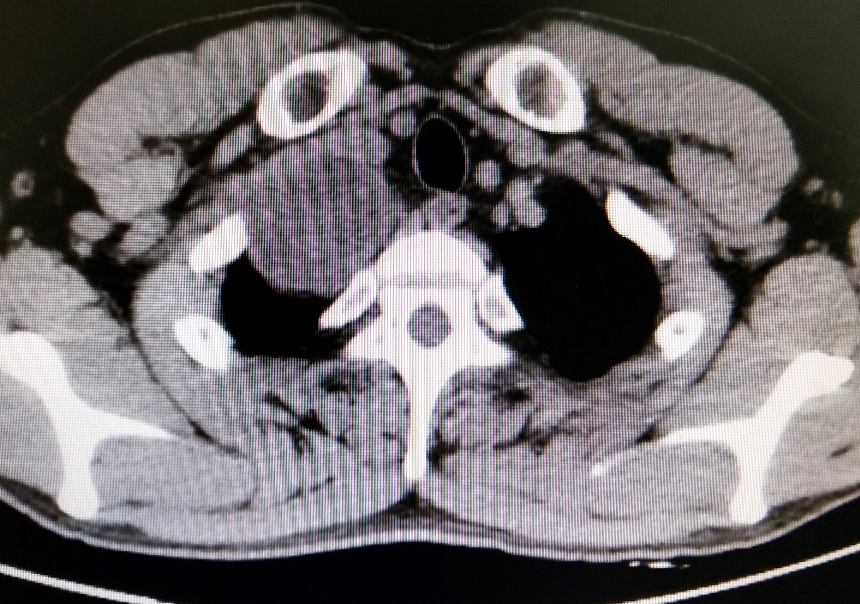

▲术前术后影像

郑志民主任为苏先生进一步做了检查并询问了他的病史后,初步诊断为“右上纵隔巨大肿瘤,神经鞘瘤可能性大”,需要住院手术治疗。在苏先生住院进行了一系列检查后, 郑志民主任发现,他体内的肿瘤不仅体积大(直径约7cm),而且位置深(胸膜顶),紧邻大血管及右侧锁骨,手术难度大,遂决定向杭州的树兰医院胸外科朱理主任汇报并立即组织胸外科全科进行科内讨论。

据郑志民主任介绍,苏先生的肿瘤巨大,且位置深,位于胸膜顶,紧邻大血管及右侧锁骨,这个位置的肿瘤对胸外科医生是一个巨大的挑战,锁骨切开是一个选择,但是考虑到手术如果采取切断锁骨的方式,会对锁骨的损伤非常大,手术风险性非常大,稍有不慎,就会损伤血管造成大出血的状况。这就要求主刀医生具有丰富的手术经验和过硬的显微外科技术。所幸在树兰医院朱理主任的助力下,经过1个半小时的努力,在微创下手术顺利完成,完成一个精彩的“探囊取物”。